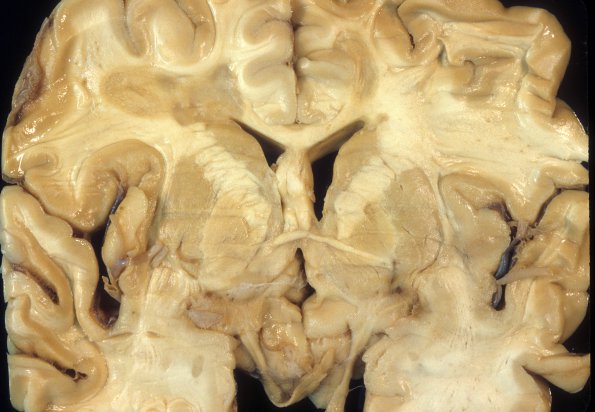

MS - Chronic Active Plaque

2C4 MS, chronic active (Case 2) A3

Nearby deeper cut section shows a similar hybrid appearance.